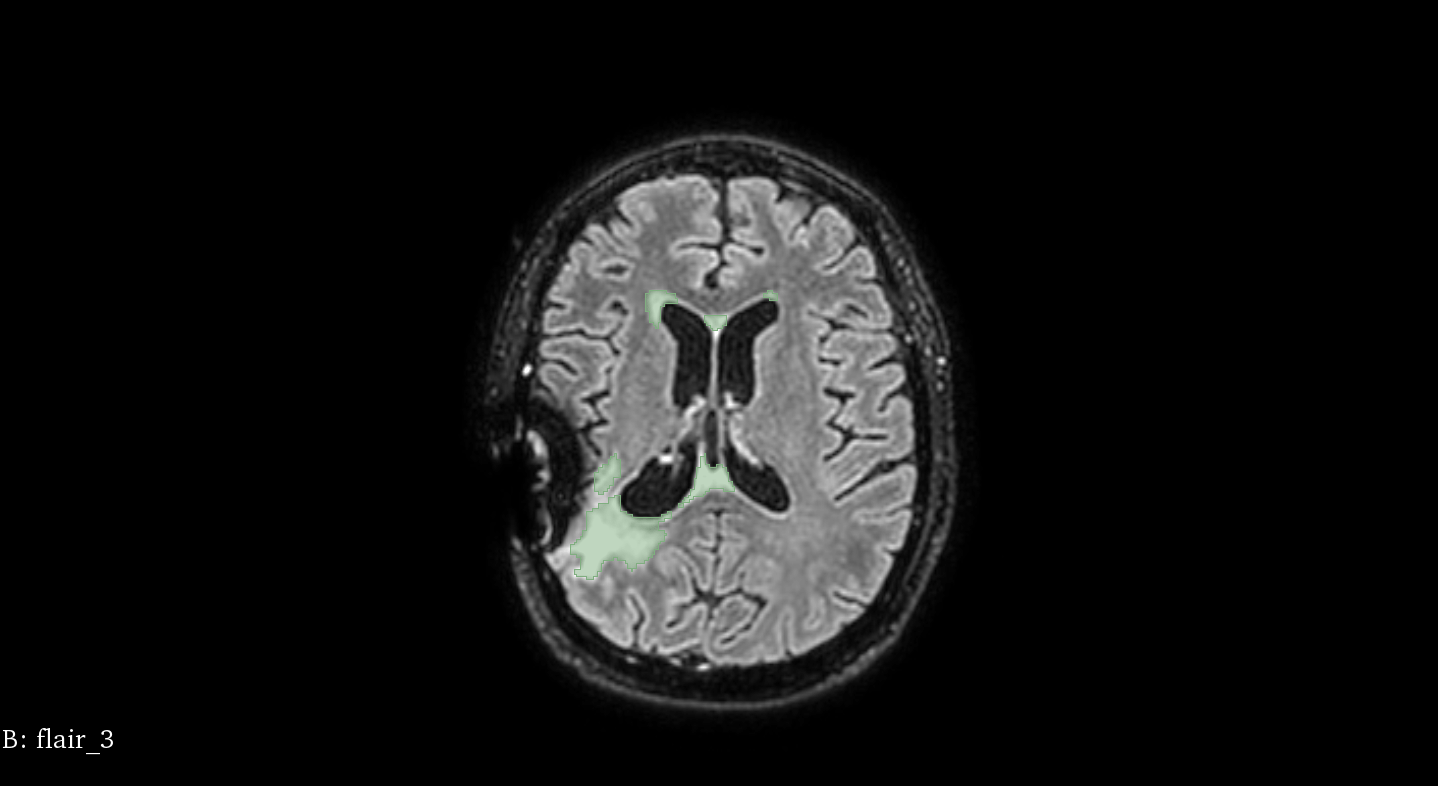

Patient 58

t=

14